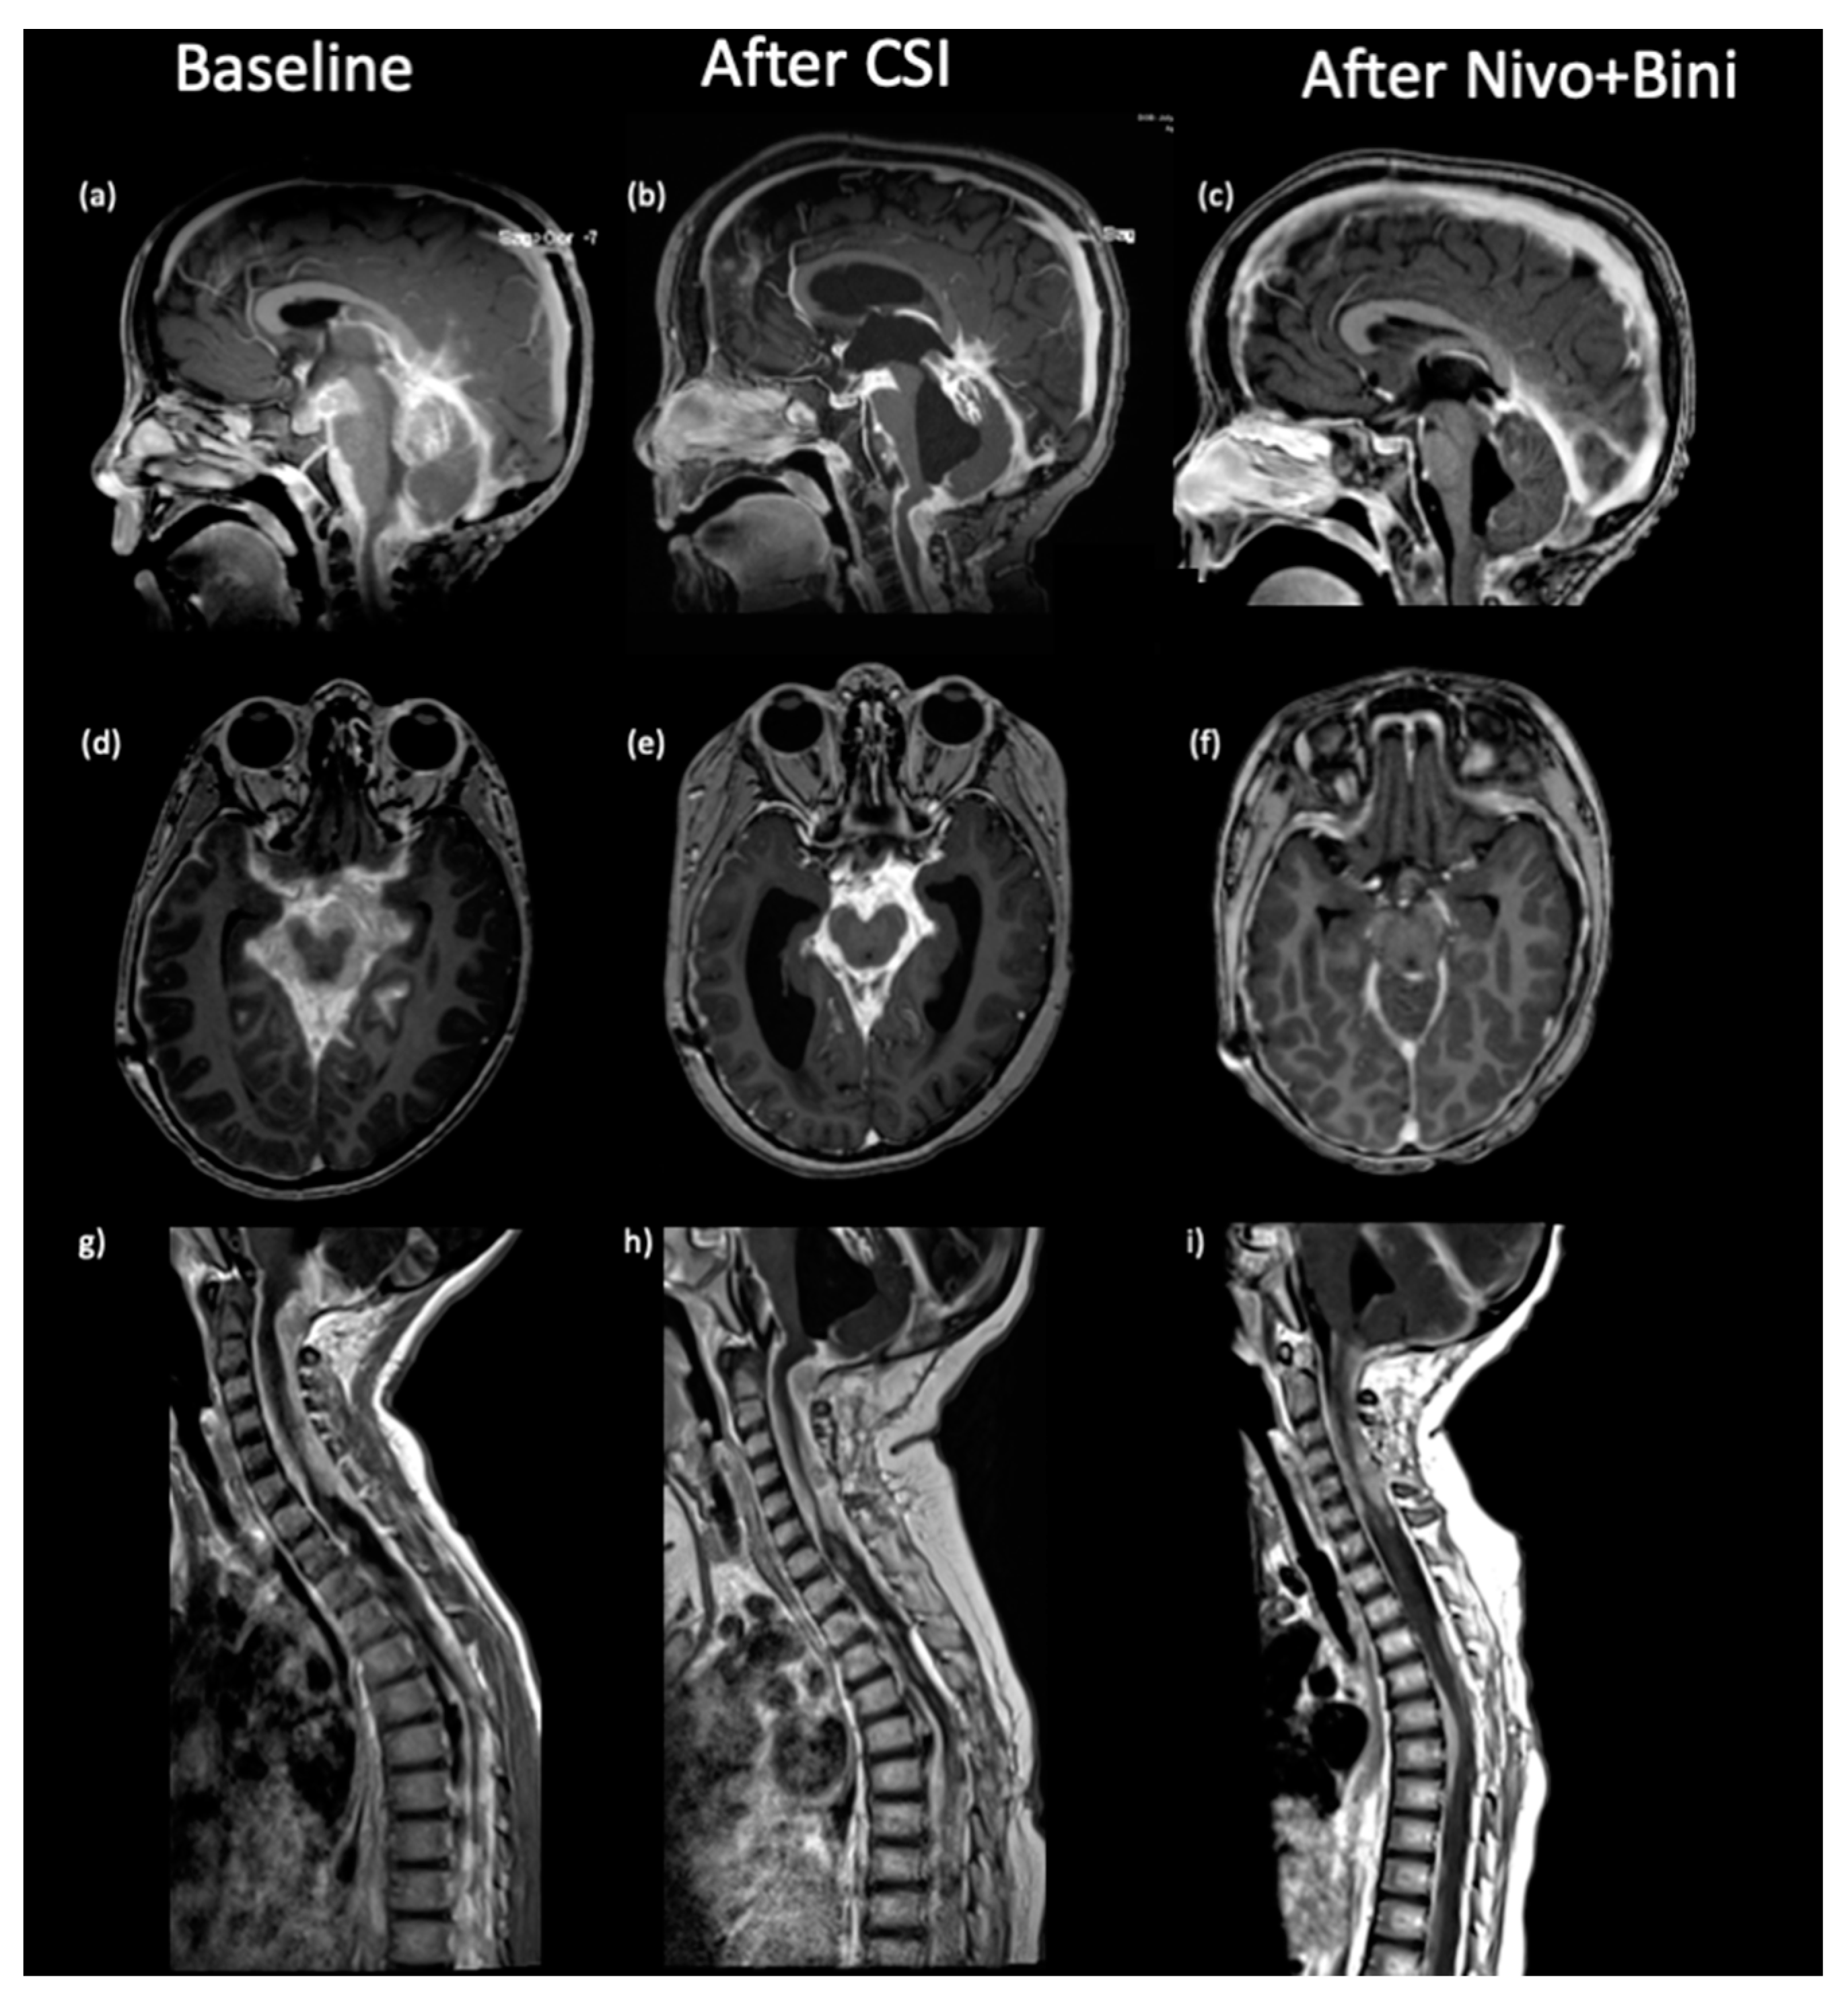

2. Case Presentation